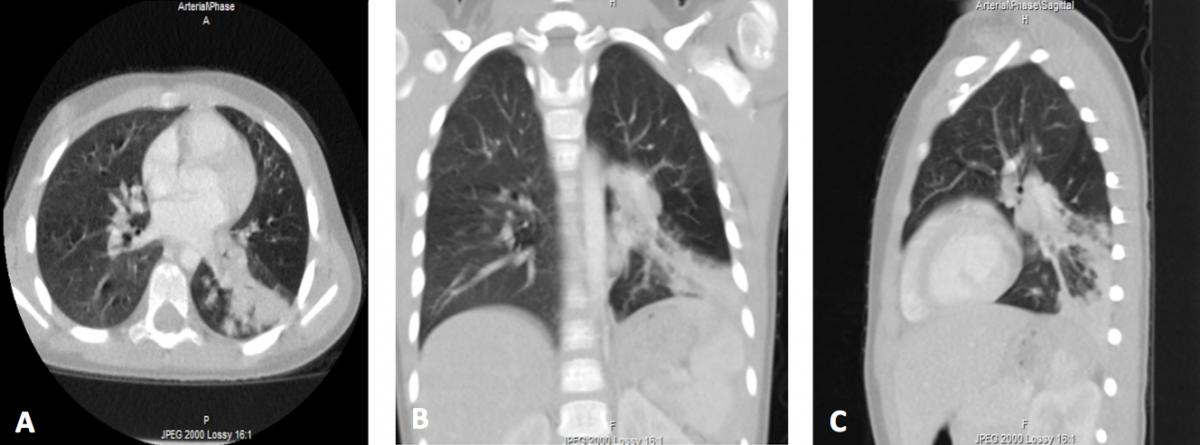

These findings, along with recurrent fever and fatigue in the context of frequent, recent pneumonias, prompted concern for possible empyema, pleural effusion, or pulmonary sequestration. Chest computed tomography (CT) with contrast demonstrated dense, organized consolidation and obliteration of the associated lobar bronchus but no systemic arterial supply or pleural fluid (Figure 2).

Figure 2. Axial (A), coronal (B), and sagittal (C) contrast-enhanced CT images demonstrating left lower-lobe bronchial obstruction.